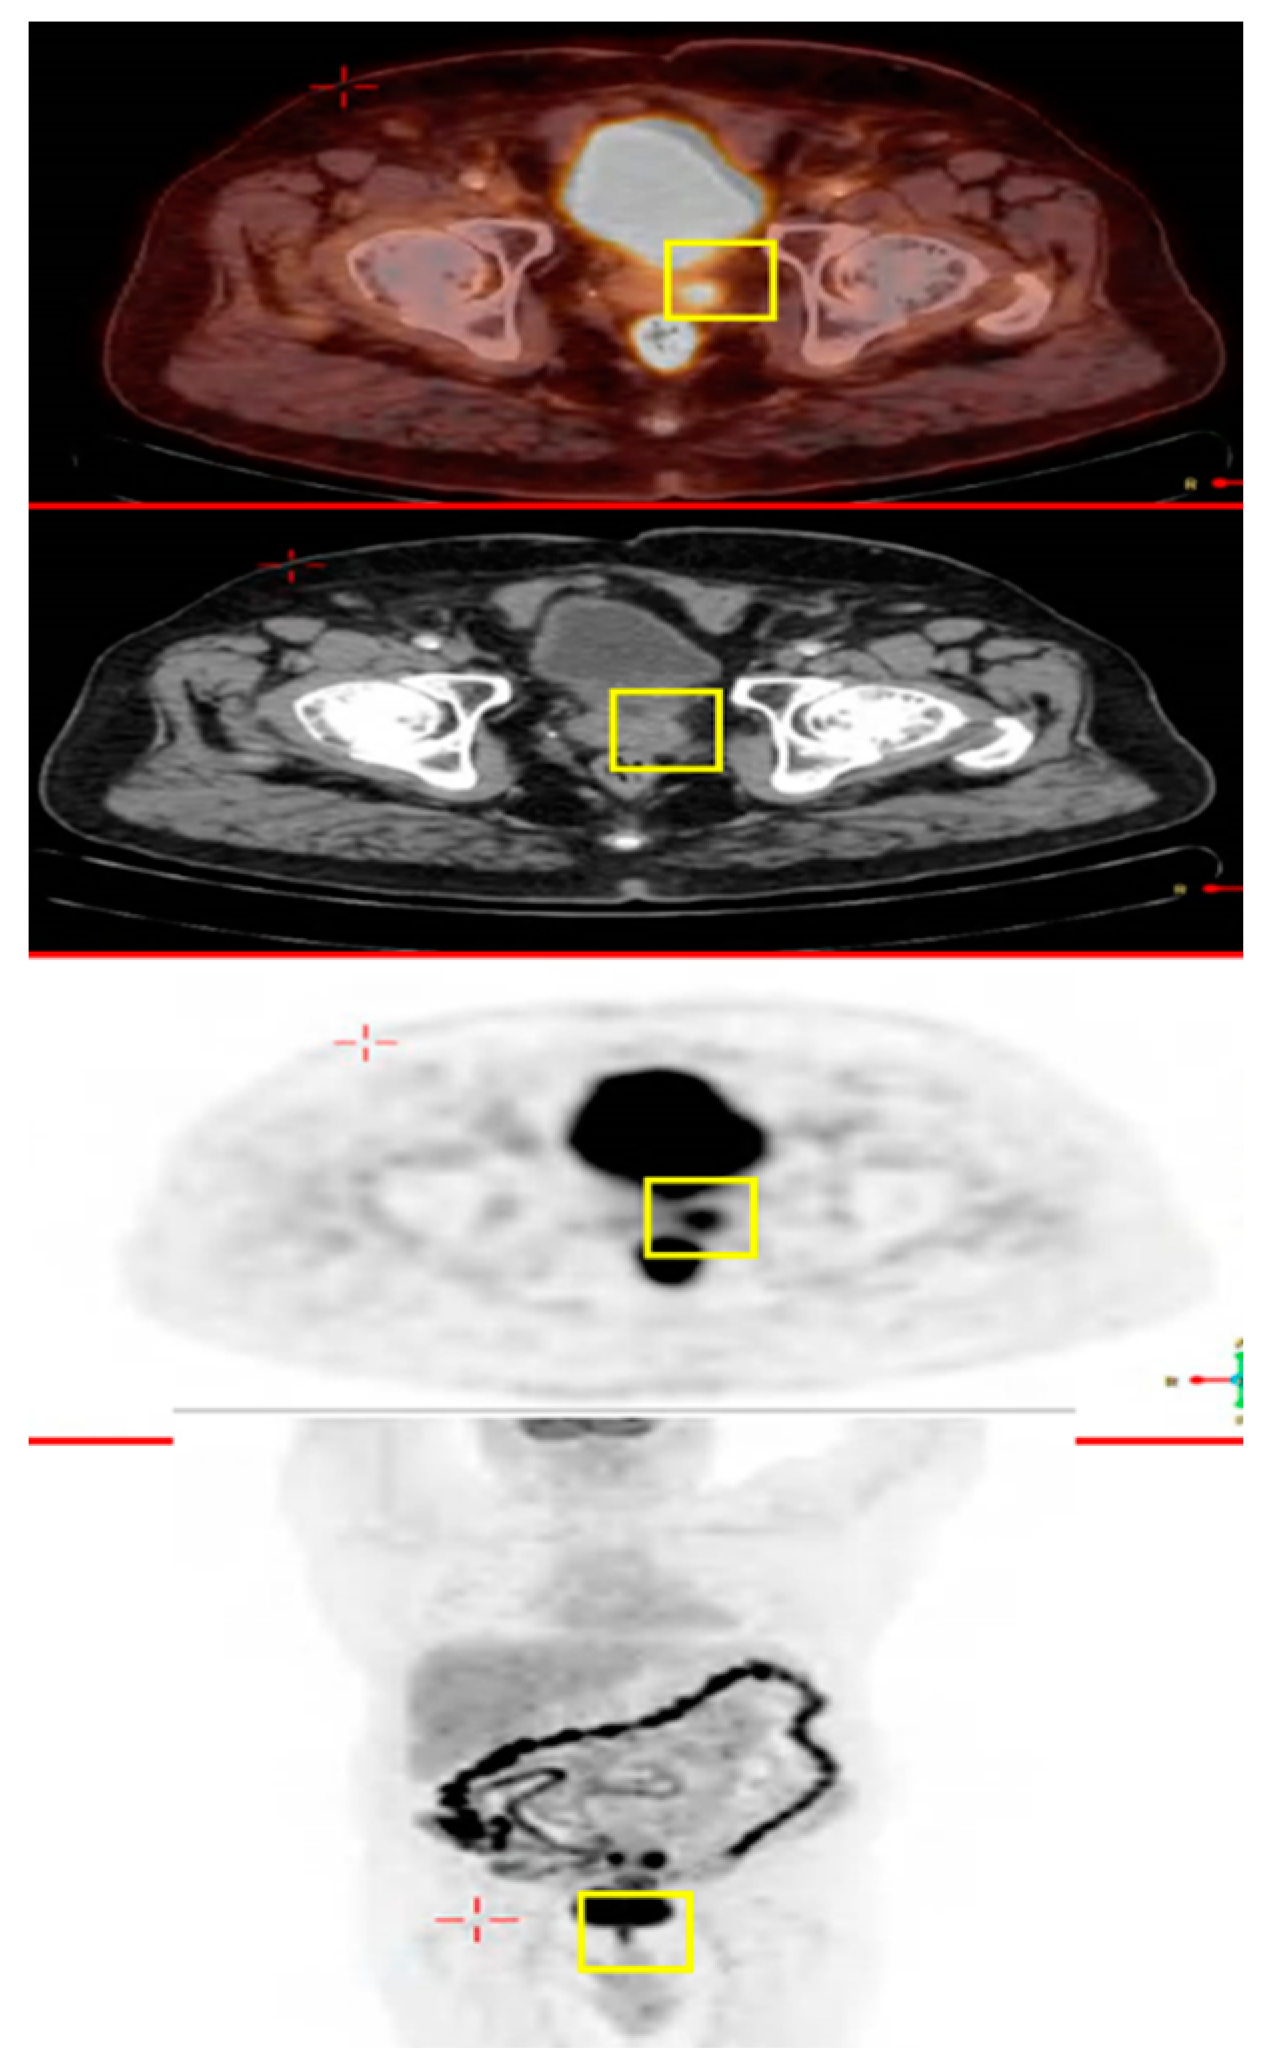

2.1. A 69 Year Old Male with Colon Cancer Metastasized to the Prostate Gland

| 3 | 63 | M | Pancreatic Adenocarcinoma | Heart | PET-CT Histopathology | FOLFIRINOX |